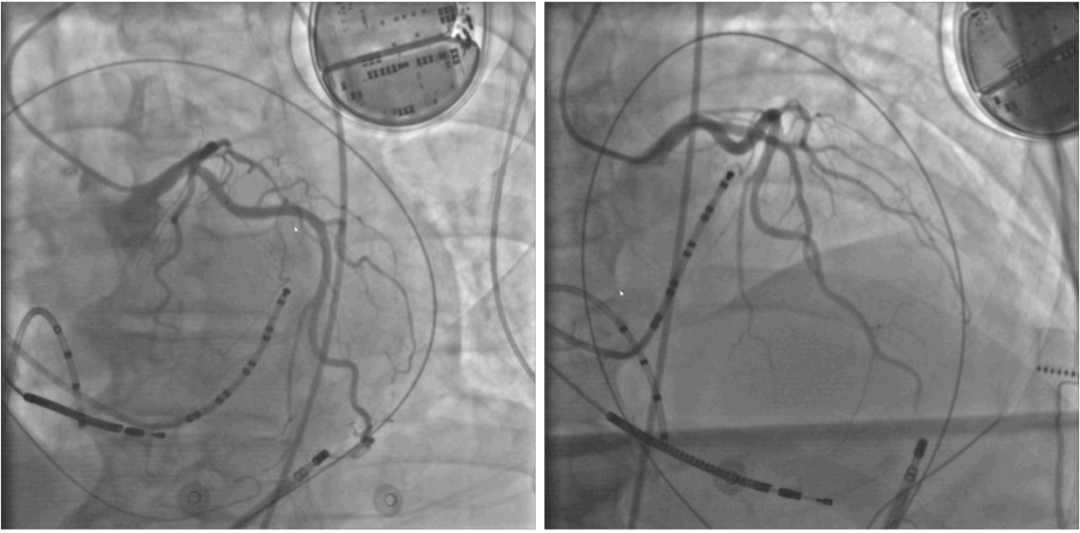

图片

经剑突下途径干性心包穿刺

因患者超声心动图提示左室下侧壁基底段呈瘤样膨出,故首先行冠脉造影检查,结果未见明显异常,排除冠脉病变。之后在窦性心律下行心内膜侧电压标测,未发现有低电压区,提示心内膜基质无明显异常;继而经心包行心外膜面电压标测,在左室下侧壁室壁瘤区附近发现大片低电压和瘢痕区以及异常心室激动电位。在诱发室速后行激动标测时,患者心室率高达270bpm,甚至蜕化为室扑、室颤,心脏停止有效射血,有创血压的压力波形曲线消失,ECMO的支持有效地维持了血压、血氧,阻断了循环崩溃,同时,在ECMO的强力支持下,术者有充足的时间进行激动标测,无需为维持血流动力学而立即电击复律,为手术的顺利完成赢得了宝贵的时间和机会。之后,在冠脉造影引导下,确定消融区域避开了冠状动脉后,在低电压区域内进行基质改良消融。最后通过心室程序刺激证实无临床持续性室性心动过速发作,提示消融成功。术后ECMO顺利撤机,患者转入CCU病房未再发作室性心动过速,术后七天好转出院。

冠脉造影及大头电极消融靶点位置